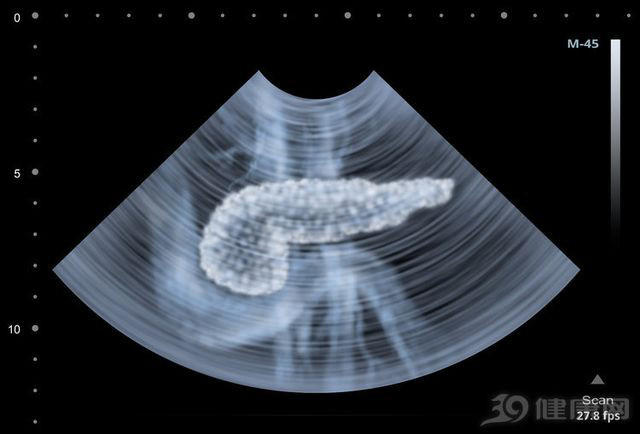

![]() |

| Vị trí tuyến tụy ẩn sâu trong bụng nên rất khó phát hiện triệu chứng |